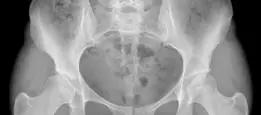

قطع العظم حول الحقي بيرنيز: حل دائم لخلل التنسج الوركي واستعادة جودة الحياة

عملية قطع العظم حول الحقي بيرنيز هي إجراء جراحي فعال لعلاج خلل التنسج الوركي، حيث يتم إعادة توجيه التجويف الحقي لتحسين تغطية رأس الفخذ واستقرار المفصل، مما يخفف الألم ويمنع تطور التهاب المفاصل، وتوفر حلاً طويل الأمد للمرضى.